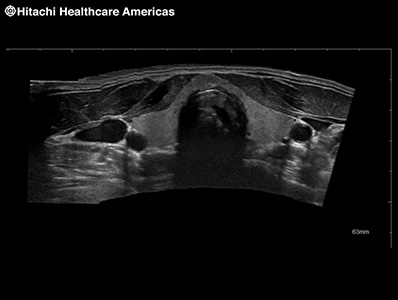

Provides an extended field-of-view image created from a series of real-time images. As the user moves the transducer across the area of interest a larger image is created that provides clearer spatial relationship information of anatomy and structures. This is especially helpful in assessing structures that are larger than the transducer field of view.